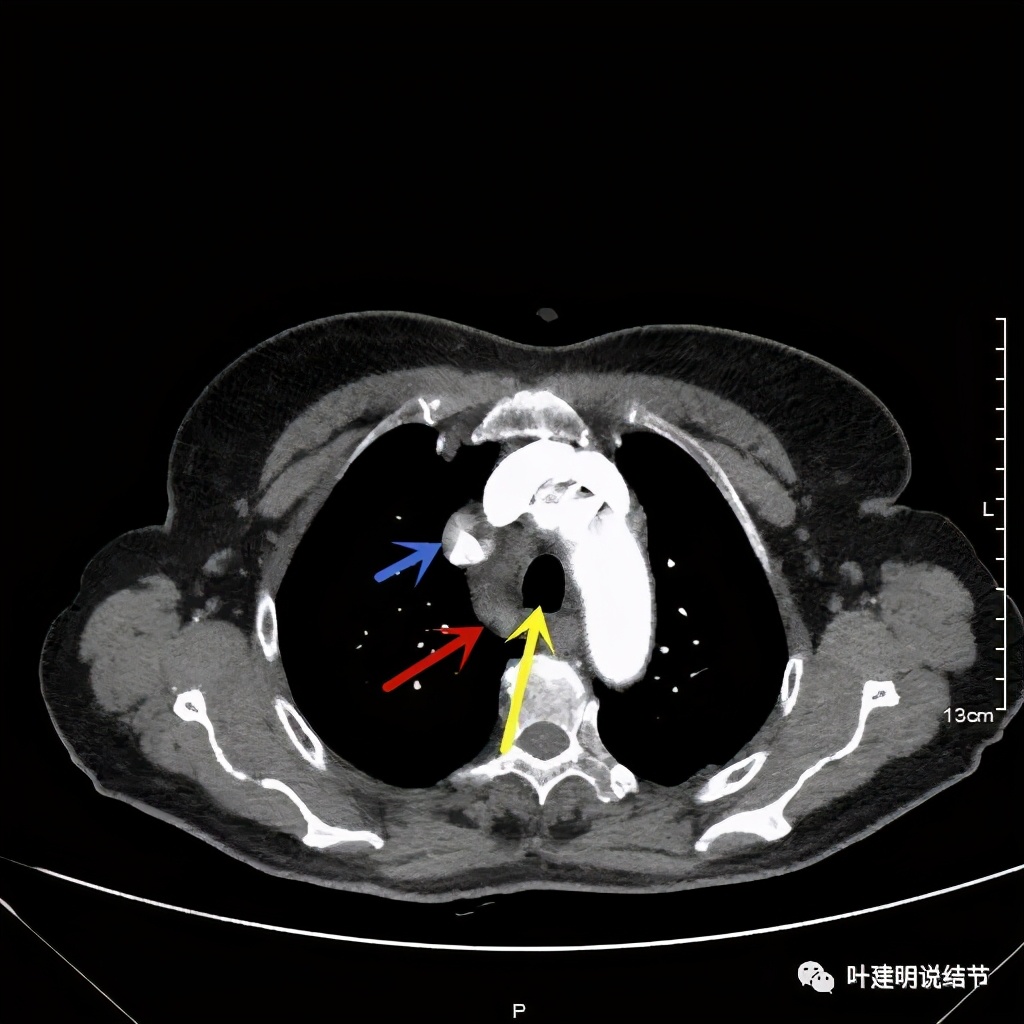

上图红色示肿瘤,黄色示气管,蓝色示上腔静脉

上图红色示肿瘤,黄色示气管,蓝色示上腔静脉,肿瘤已经快要消失了的层面,它距离隆突只有2点几厘米了,位置很低